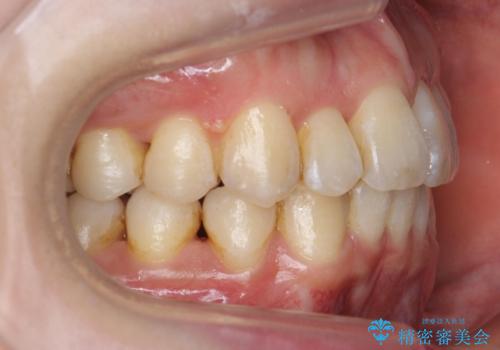

右の上下の混雑が激しく、通常は上下左右4本抜歯も相当する症状でした。

右のみ上下1本ずつ抜歯した場合、上の正中がずれる恐れもあります。

右下の臼歯が内側に倒れこみ、小臼歯部分はすれ違い咬合、大臼歯も反対咬合となっていました。

歯の大きさを計測したところ、下の歯がとても大きく、4本抜歯したとしても奥歯のかみ合わせを交互にするのが難しい状態でした。